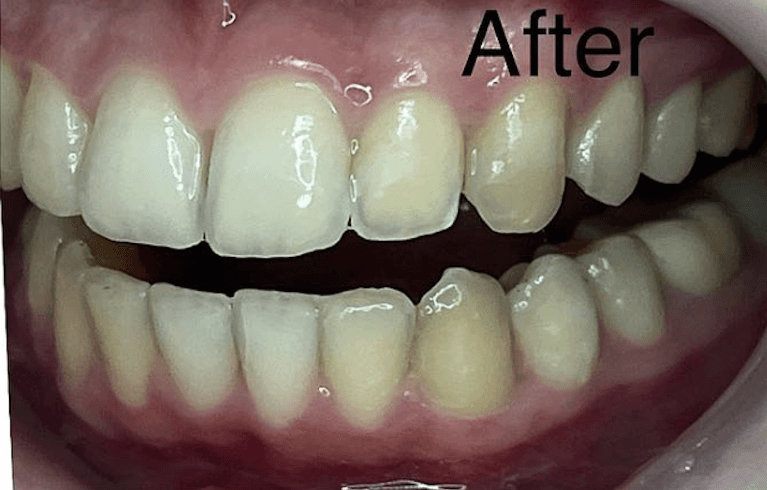

Invisalign Orthodontic treatment completed in 8 months to straighten teeth and improve esthetics.